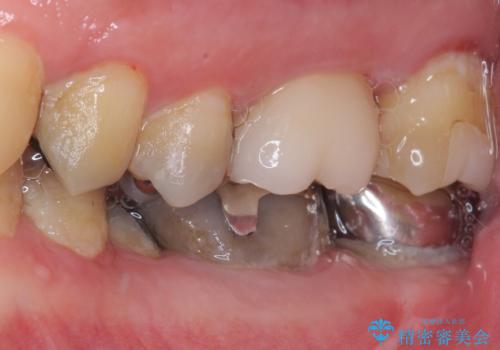

- 奥歯に食べ物がよくはさまるのが気になるとのことで来院された患者様です。

フロスをすると第一大臼歯の部分が引っ掛かり段差になっていることがわかりました。

インレーの範囲が大きいためオールセラミッククランにて補綴することとしました。

前後の歯の詰め物のやり替えも提案しましたが、患者様の希望により第一大臼歯から治療を始めていくこととしました。